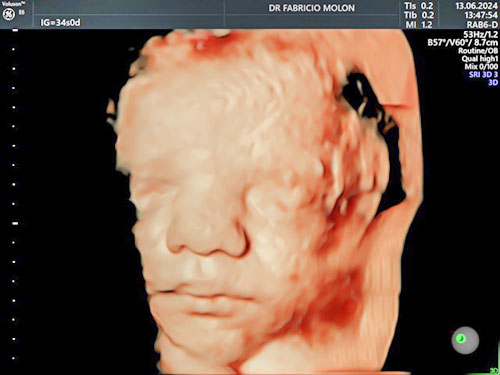

US 3D/4D e 5D com HD live

É possível conhecer o rostinho do bebê ainda na barriga, com a ultrassonografia 4D e 5D! Essa tecnologia permite ver a face do bebê com uma precisão incrível, além de poder gravar as imagens.

O exame traz melhores imagens quando realizado entre 26 e 30 semanas.